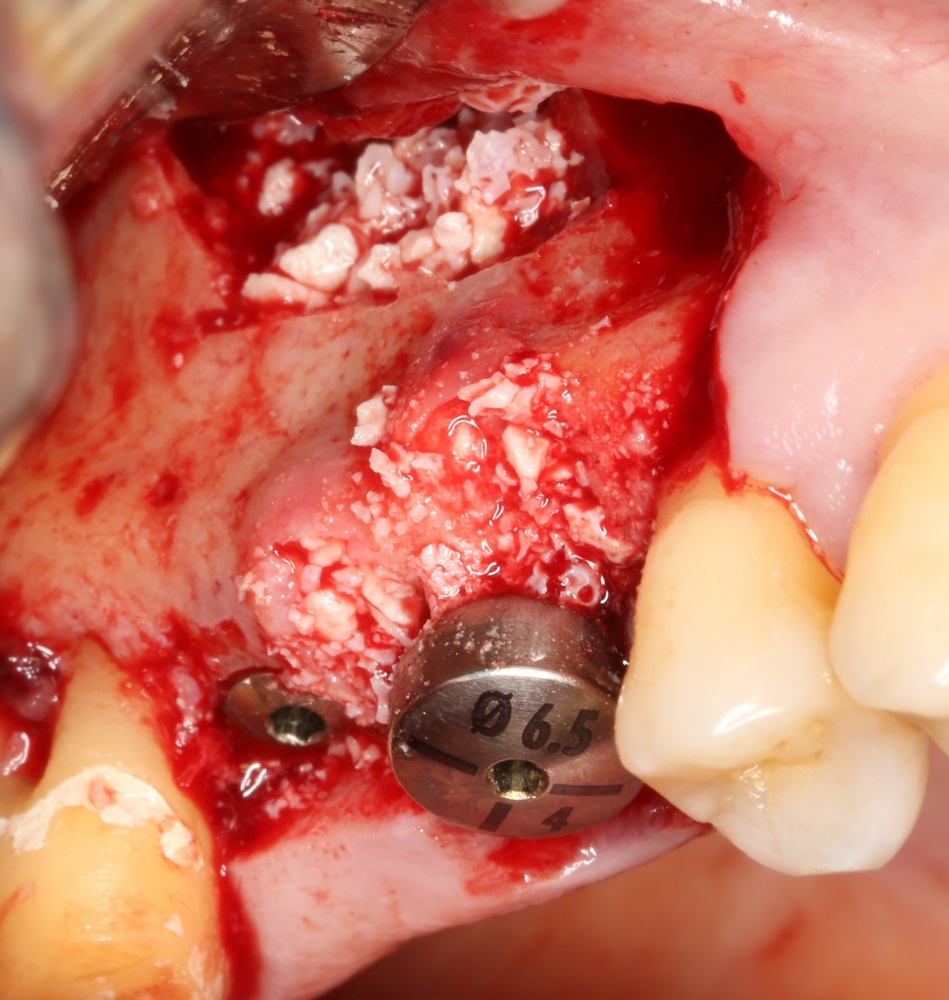

Как выбрать графт для заполнения субантрального пространства? И на какие свойства графта нужно обратить максимум внимания?

Что делать, если вдруг случилась перфорация слизистой оболочки?